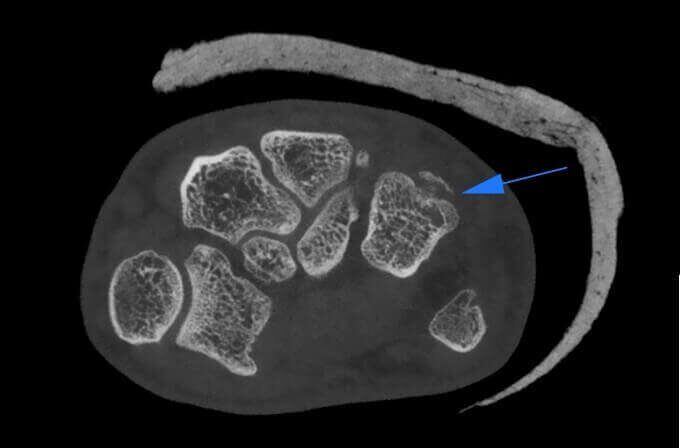

Microfratture di Scafoide